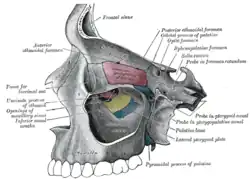

Base do crânio. Superfície superior. Parede medial da fossa nasal esquerda.

Parede medial da fossa nasal esquerda. Paredes da cavidade nasal esquerda.